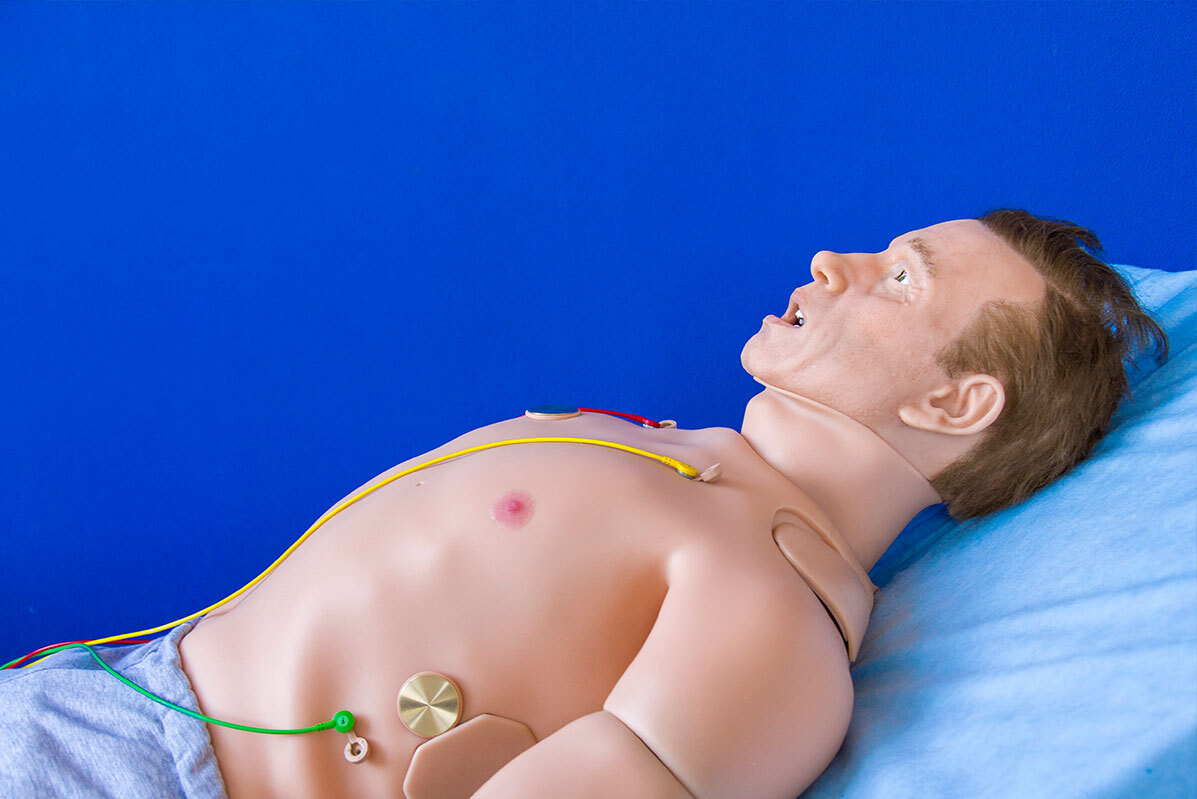

علامة تحذير مقلقة في معدتك لاحتمال النوبة القلبية!

يمكن لأعراض نوبة القلب أن ترسل موجات صدمة عبر جسمك، ما يتسبب في ظهور الأعراض في أماكن مفاجئة.

وتعد النوبة القلبية حالة طبية طارئة خطيرة حيث يتم منع إمداد القلب بالدم فجأة، عادة بسبب جلطة دموية. ونظرا لموقعه، فإن ألم الصدر يعتبر السمة المميزة للأزمة القلبية. وكما أوضح الطبيب العام، ألكا باتيل، لموقع "إكسبريس": "في المجال الطبي، كان الوصف الكلاسيكي للنوبة القلبية دائما "ألما مركزيا ساحقا في الصدر".

ومع ذلك، فإن التركيز فقط على ألم الصدر لا يعكس النطاق الكامل للأعراض المحتملة، ويمكن أن يكون له عواقب وخيمة.

وكشف باتيل أن هناك مواقع رئيسية أخرى في جسمك يمكن أن تشير أيضا إلى نوبة قلبية. وحذر من أن منطقة المعدة هي أحد أكبر ضحايا النوبات القلبية.

وقال: "عندما تموت عضلة القلب بسبب نقص الأكسجين، تطلق الأنسجة المصابة مجموعة من المستقلبات، بما في ذلك حمض اللاكتيك، الذي يحفز الألياف العصبية التي تسبب الغثيان والقيء".

أعراض محتملة غير معروفة للإصابة بالنوبة القلبية

وأضاف أن "العصب المبهم الطويل" الذي يتجه إلى القناة الهضمية، يرتبط أيضا بالقلب، وهذا ما يتهيج أثناء الأزمة القلبية.

وقال باتيل: "إذا كنت تعاني من قيء غير مبرر، أو غثيان مستمر، خاصة عند إجهاد نفسك، فقد تكون هذه إشارة إنذار".

ويعد تعرق راحة اليد من الأعراض المدهشة الأخرى المرتبطة بنوبة قلبية.

وأوضح الدكتور باتيل: "يتعرق الجسم لإبقاء درجة حرارة الجسم منخفضة؛ إذا كان على قلبك أن يعمل بجهد أكبر لضخ الدم عبر الشرايين الضيقة، فسترتفع درجة حرارتك كلما استهلكت المزيد من الطاقة وبالتالي ستتعرق".

وغالبا ما يتجاهل الناس أنهم يعانون من نوبة قلبية ويؤخرون طلب الرعاية الطبية.

كيفية منع النوبة القلبية

يعد إجراء تغييرات في نمط الحياة الطريقة الأكثر فعالية لمنع الإصابة بنوبة قلبية (أو الإصابة بنوبة قلبية أخرى).

ووفقا لـ NHS، هناك ثلاث خطوات رئيسية يمكنك اتخاذها للمساعدة في منع النوبة القلبية.

• تناول نظام غذائي صحي ومتوازن.

• لا تدخن.

• حاول أن تحافظ على ضغط دمك عند مستوى صحي.

ويمكن أيضا أن تقلل ممارسة التمارين الرياضية بانتظام من المخاطر، من خلال مساعدتك على إنقاص الوزن، ما يساعد على خفض ضغط الدم.

المصدر: إكسبريس